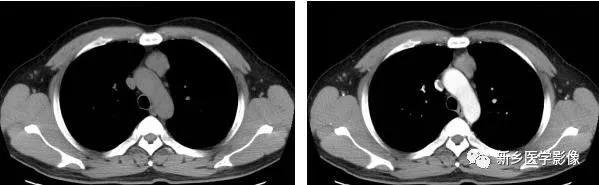

非侵袭性胸腺瘤CT图像

a. CT平扫示前上纵膈主动脉弓与胸骨间软组织密度肿块,密度均匀,边缘浅分叶状 b. CT增强示肿块均匀强化,肿块与主动脉弓之间脂肪间隙清晰